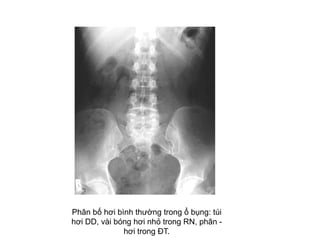

Phân bố hơi bình thường trong ổ bụng: túi

hơi DD, vài bóng hơi nhỏ trong RN, phân -

hơi trong ĐT.

KHÍ BÌNH THÖÔØNG TRONG XQ

BUÏNG KHOÂNG SÖÛA SOAÏN

• Hôi trong daï daøy – taù traøng

• Ít hôi trong ruoät non

• Hôi trong ñaïi traøng goùc laùch, goùc gan, tröïc traøng

• Ít hôi laám chaám vuøng manh traøng